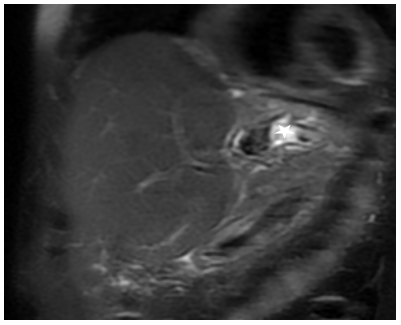

Considering that an increase in pressure in the stomach causes an increase in the tone of the LES, we applied abdominal compression while taking barium in a horizontal position. In patients without GERD symptoms, peristalsis of the esophagus despite abdominal compression pushed the contrast agent into the stomach without delay (Figure 1, a, b & c). In some patients during abdominal compression between the esophagus and stomach, filled with barium, a gap appeared without contrast material (Figure 1d). These observations showed that in healthy individuals it is impossible to measure the length of the LES because the LES does not close under abdominal compression. At the same time, based on manometric and histological studies, it is known that in some patients with GERD the length of the LES is shorter than normal. It is shortened due to weakening and opening of the abdominal part of the LES [20,25,44-46]. To measure the length of the LES, to eliminate the possibility of error because of the simultaneous contraction of the crural diaphragm (CD), I performed an X-ray of the EGJ after 30 seconds of abdominal compression. As Shafik et al showed that “The CD response disappeared when straining was sustained for more then 15-18 seconds (mean 16.8 ± 1.2) and was not evoked after frequent successive straining… due to the fact that the CD consists of striated muscle fibers which are easily fatigable and cannot remain contracted for long period” [47]. Thus, abdominal compression for 30 seconds allowed only the length of the LES to be measured, because by this time the CD was already in a relaxed state. It should be noted that the strength of abdominal compression is not of significant importance, since contraction of the anterior abdominal wall is a standard response of the child to abdominal compression. In a previous study to determine the standards, we selected 42 studies in which abdominal compression resulted in LES contraction. These were patients with mild GERD, in whom GERD symptoms were either absent or appeared less than a month ago. Therefore, we considered that the length LES did not have time to change significantly compared to the norm. On radiographs, we measured the width of the esophagus and the length of the gap between the barium in the esophagus and stomach (see Figure 1). To get the true dimensions, we multiplied the readings measured on the X-ray by the projection distortion factor. The latter is equal to the ratio of the true L-1 height for a given age (Table 1) to the height of its image on the roentgenogram [26].

Figure 1. The passage of the bolus through the EGJ during abdominal compression in the horizontal position of patients. (a, b, c) In a patient without GERD symptoms, the peristaltic wave overcame the increased tone of the LES, because of which barium passed into the stomach without delay and the LES could not be detected. (d). In a patient with GERD, as evidenced by longitudinal folds in the esophagus and at the level of the LES, abdominal compression resulted in LES contraction. Its length can be measured as the distance without contras medium between the esophagus and the stomach. Since the height of D-10 is approximately 2 cm, the true length of the LES can be calculated. It is 2.4 cm.